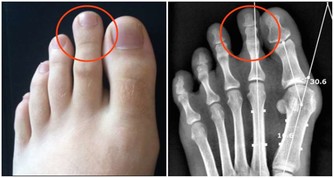

【3】膀胱疾病

晚上頻繁起夜上廁所,有可能是膀胱疾病引起的,膀胱保持正常功能,才可以儲存尿液。

但如果莫名其妙出現尿頻尿急,夜尿增多,很可能是膀胱出現了惡性腫瘤或者是膀胱結石,導致膀胱儲存尿液的能力降低,伴隨著排尿頻繁的表現。